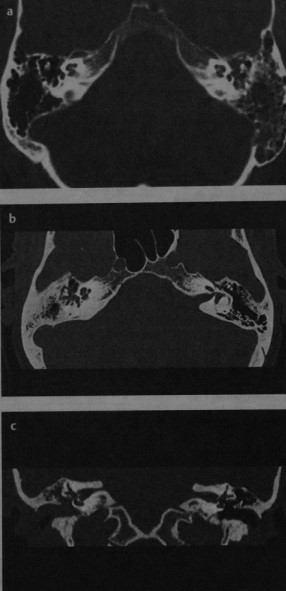

МРТ внутренних слуховых проходов в аксиальной проекции:

(а) Т1 до введения контраста.

(б) Т1 после введения гадолиния (обратите внимание на усиление сигнала от сигмовидного синуса и слизистой околоносовых пазух).

(в) Т2 (ликвор и глазные яблоки выглядят яркими),

а, мозжечок; b, сосцевидный отросток; с, четвертый желудочек; d, сонная артерия; е, сигмовидный синус;

f, улитка; д, сонная артерия; h, височная доля; i, мостомозжечковый угол (обратите внимание на слуховой и нижний вестибулярный нервы, которые входят во внутренний слуховой проход).